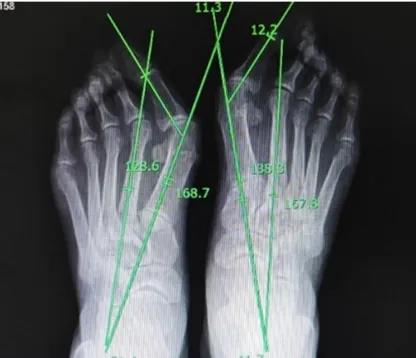

双足拇外翻畸形明显,拇囊处突出,且伴有双足拇趾旋前畸形,第二趾锤状指畸形,局部胼胝体形成。

左足HVA 51.4°,IMA 11.3°;右足HVA 41.7°,IMA 12.2°